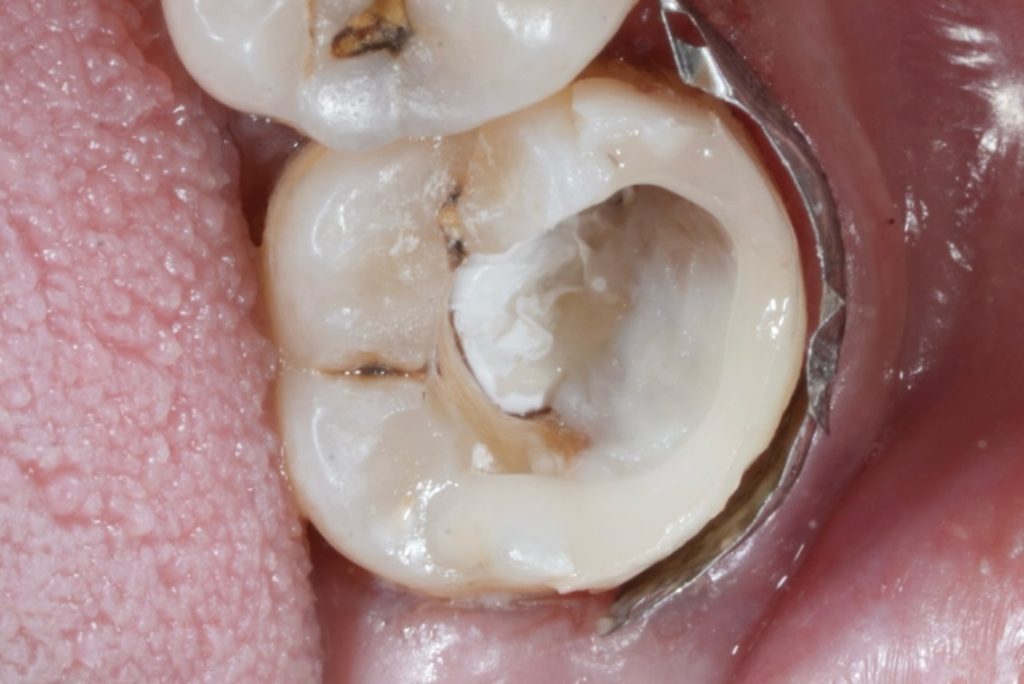

4 Deep Margin Elevation (DME)

The deep cervical margin was elevated using a layer of GC EverX Posterior, reinforced with a thin bonded layer of flowable composite.

This fiber-reinforced base acts as a stress-absorbing dentin replacement and facilitates better cervical seal (Fig 7).

6️⃣ DME with GC EverX Posterior